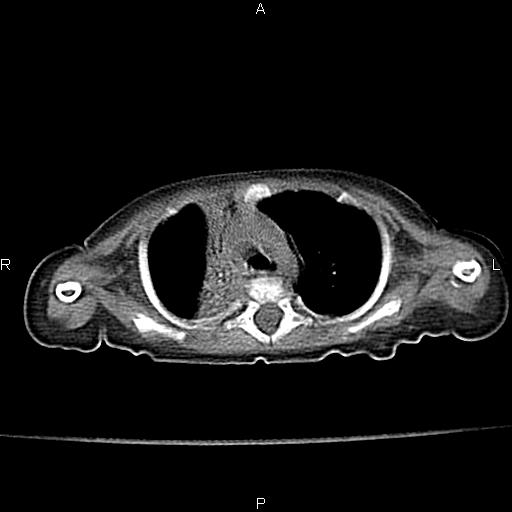

以下是引用jsdtd在2010-7-26 14:42:00的发言:[br]胸腺呈帆状,体位所致,没事。

以下是引用aa13877358820在2010-7-26 12:35:00的发言:[br]男性,三个月,卧位胸片,咳嗽、气促、发热14天,两肺闻及细小水泡音。[br]